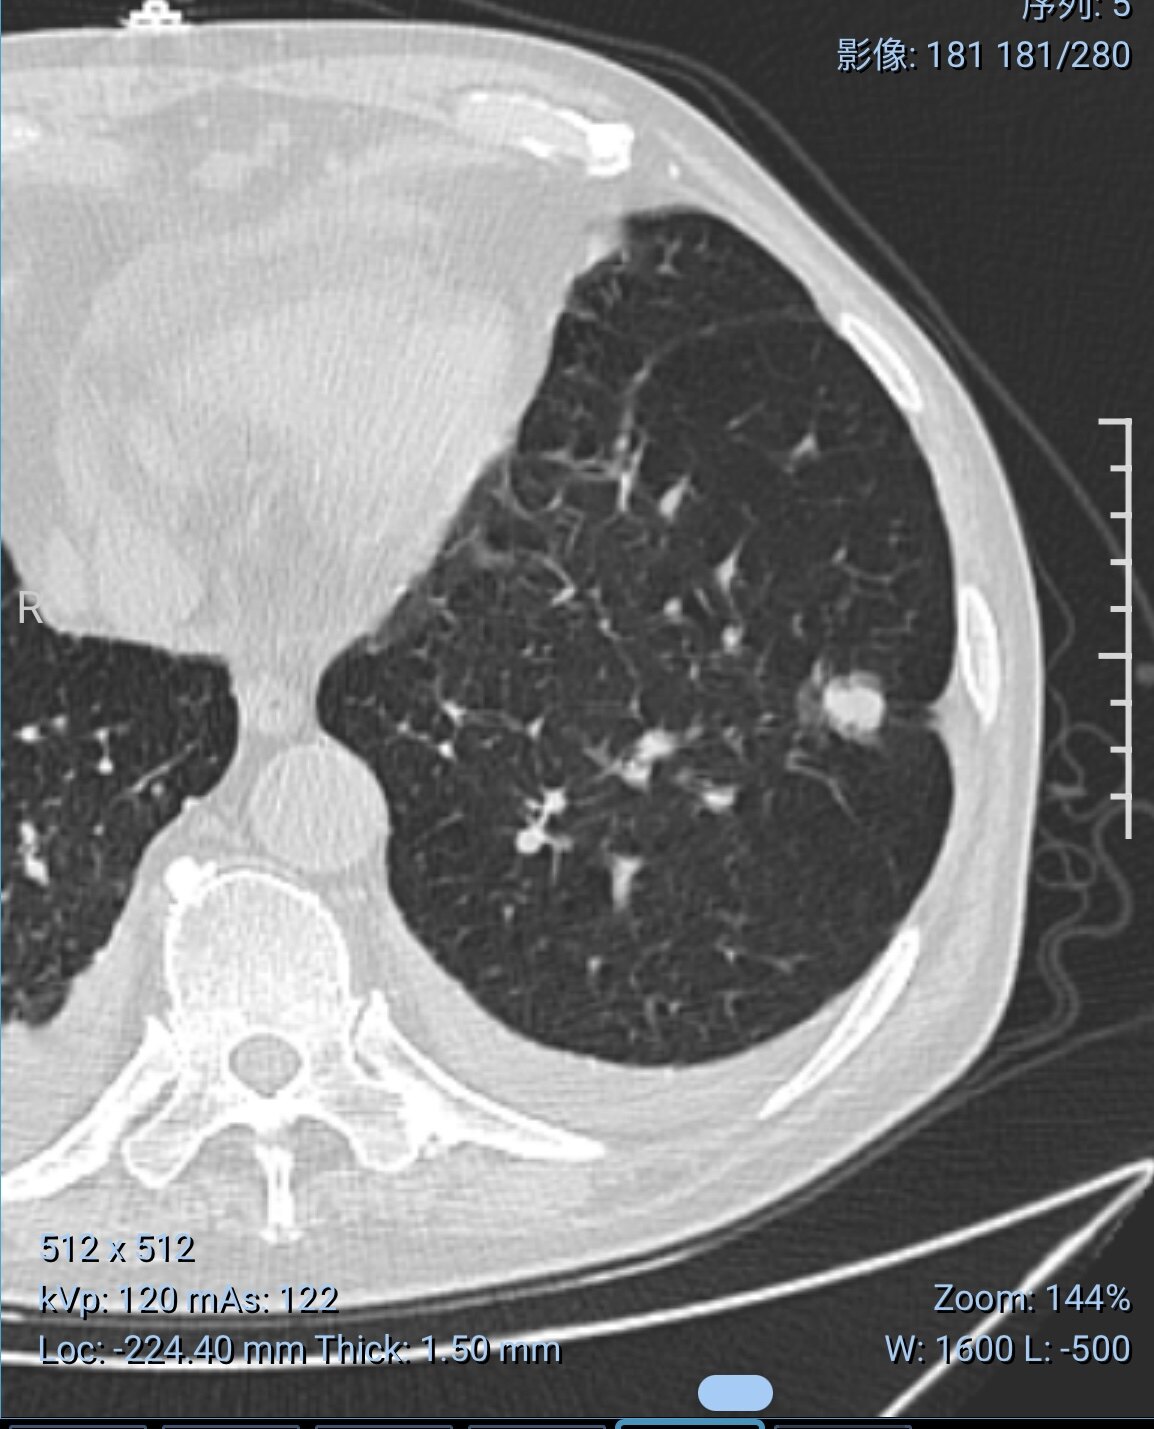

由于早期肺癌基本上都是無癥狀的肺部結(jié)節(jié)影,而我們以前常規(guī)胸部體檢都是做胸片,分辨率比較低,難以發(fā)現(xiàn)1厘米左右的結(jié)節(jié)和磨玻璃密度結(jié)節(jié),使得肺癌臨床上早期診斷率比較低。隨著CT的普及和發(fā)展,肺結(jié)節(jié)的發(fā)現(xiàn)率越來越高,其中高危結(jié)節(jié)讓很多人都心情緊張甚至寢食難安。針對肺部結(jié)節(jié),尤其是有分葉征、毛刺征、胸膜牽拉征或者多次復(fù)查沒有明顯吸收減小的磨玻璃結(jié)節(jié),臨床上不能排除惡性腫瘤或者癌前病變的可能,屬于高危結(jié)節(jié)。那么,發(fā)現(xiàn)了肺部高危結(jié)節(jié)或者多次隨訪結(jié)節(jié)沒有吸收減小我們有哪些處理方法呢?除了經(jīng)典的外科手術(shù),目前臨床上內(nèi)科微創(chuàng)介入消融也是個非常好的處理方法。介入消融操作原理是運用微波消融針,以熱消融的形式使結(jié)節(jié)病灶發(fā)生細胞凝固壞死,部分結(jié)節(jié)還可以在消融同時行活檢留取病理標本,為后續(xù)治療和隨訪提供依據(jù)。依據(jù)不同的定位方式分為CT引導(dǎo)下的經(jīng)皮介入消融和導(dǎo)航支氣管鏡引導(dǎo)下的經(jīng)支氣管鏡介入消融,位于肺外周的結(jié)節(jié)適合經(jīng)皮穿刺消融,需要在CT精準定位引導(dǎo)下完成,位于肺中心的結(jié)節(jié)或者有支氣管相通的結(jié)節(jié)適合經(jīng)支氣管鏡介入消融,需要在導(dǎo)航支氣管鏡精準引導(dǎo)下完成。具體治療方案需要看結(jié)節(jié)的位置來選擇。具有操作簡單,創(chuàng)傷小,恢復(fù)快的特點。一般住院時間3-5天,消融過程大約耗時30-60分鐘,多數(shù)患者消融后第二天即可出院。下圖是一個左下葉結(jié)節(jié),距離胸壁大約5cm。結(jié)節(jié)直徑約1.2cm,有分葉征,且隨訪一年有增長趨勢的病例,圖1是通過CT檢查規(guī)劃穿刺路徑,圖2是在CT精準定位下完成結(jié)節(jié)的經(jīng)皮穿刺消融。共計耗時25分鐘。術(shù)后第二天出院。如果大家有肺部結(jié)節(jié)帶來的困擾,歡迎您線上線下來就診。圖片里顯示的是術(shù)后皮膚穿刺點和拇指粗細的5ml注射器比較,大小約1mm,小米粒大小。